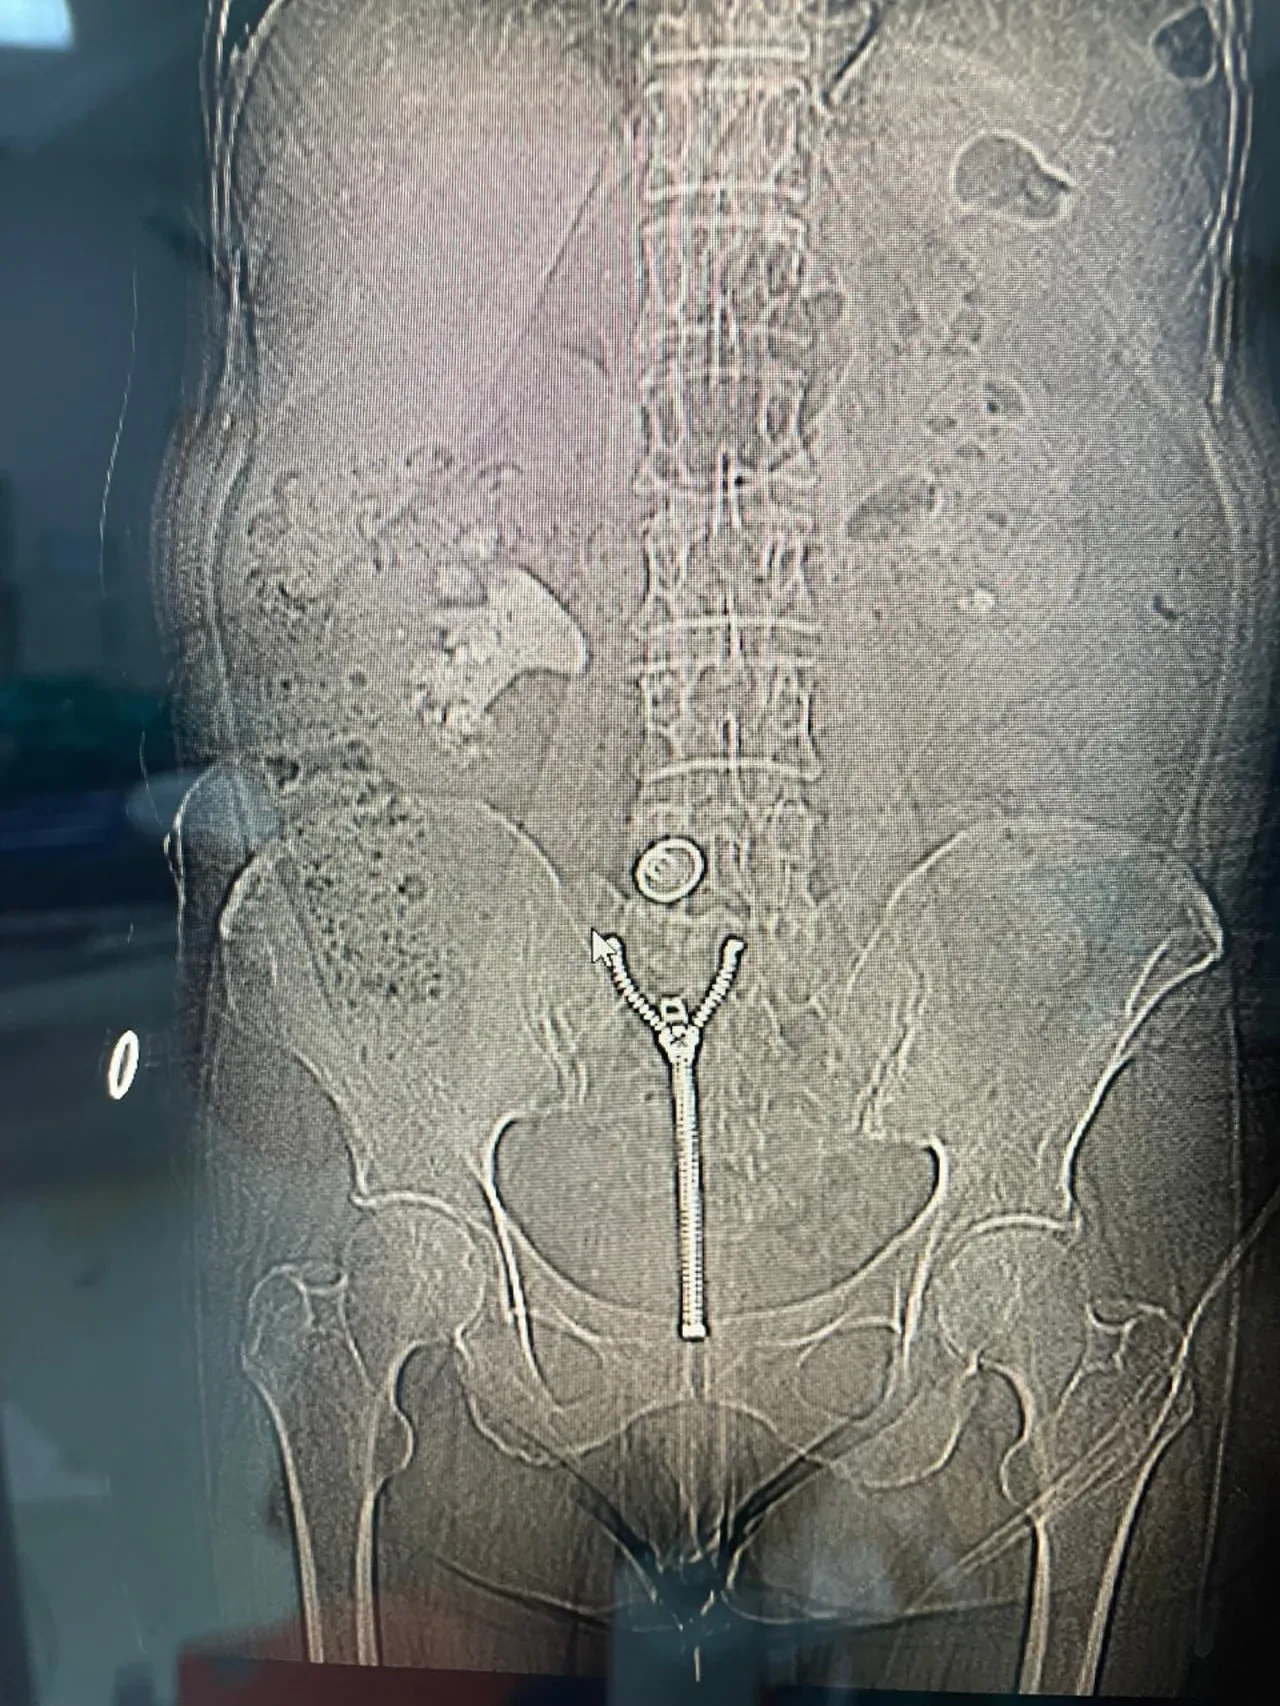

Çocukluğundan beri böbrek taşıyla mücadele eden Sabaner sağ yan ağrısı şikayetiyle doktora gitti. Yapılan tetkiklerinde böbreği tamamen dolduran 8 santimetrelik "geyik boynuzu" (staghorn) böbrek taşı görüldü.

Operasyonu gerçekleştiren Üroloji Kliniği Uzmanı Dr. Mehmet Levent Akbulut, taşın büyüklüğüne dikkat çekerek, "Hastamızın böbreğinde yaklaşık 8 santimetre çapında büyük bir taş vardı. Tıpta bu tabloya ‘staghorn', yani geyik boynuzu taşı diyoruz. Eğer bu taş alınmasaydı, böbrek fonksiyonunu tamamen kaybedebilirdi. Biz de perkütan nefrolitotomi adını verdiğimiz kapalı yöntemi tercih ettik. Tomografi yardımıyla planlama yaparak, böbreğe küçük bir delikten girip taşı parçalara ayırarak tamamen temizledik. Ameliyat sonrası hastamızın böbreği taşsız hale getirildi" dedi. Dr. Akbulut, söz konusu yöntemin açık ameliyata göre çok daha hızlı iyileşme süreci sağladığını ve bu tür kompleks operasyonların Malatya'da başarıyla gerçekleştirilebildiğini belirtti.